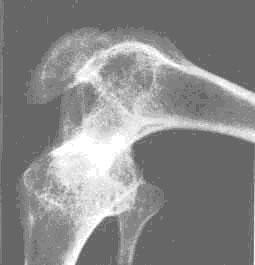

维生素D缺乏性佝偻病是怎么回事?维生素D缺乏性佝偻病这是一种小儿常见病占总佝偻病95%以上本病系因体内维生素D不足引起全身性钙磷代谢失常以致钙盐不能正常沉着在骨骼的生长部分最终发生骨骼畸形佝偻病虽然很少直接危及生命但因发病缓慢易被忽视一旦发生明显症状时机体的抵抗力低下易并发肺炎腹泻贫血等其它疾病。[1]